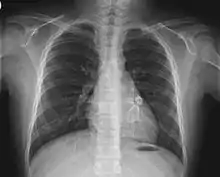

X-ray showing aneurysmal enlargement of the coronary arteries, which is a complication in a Kawasaki syndrome

Heart complications are the most important aspect of Kawasaki disease, which is the leading cause of heart disease acquired in childhood in the United States and Japan.[31] In developed nations, it appears to have replaced acute rheumatic fever as the most common cause of acquired heart disease in children.[15] Coronary artery aneurysms occur as a sequela of the vasculitis in 20–25% of untreated children.[52] It is first detected at a mean of 10 days of illness and the peak frequency of coronary artery dilation or aneurysms occurs within four weeks of onset.[48] Aneurysms are classified into small (internal diameter of vessel wall <5 mm), medium (diameter ranging from 5–8 mm), and giant (diameter > 8 mm).[31] Saccular and fusiform aneurysms usually develop between 18 and 25 days after the onset of illness.[15]

Even when treated with high-dose IVIG regimens within the first 10 days of illness, 5% of children with Kawasaki disease develop at the least transient coronary artery dilation and 1% develop giant aneurysms.[53][54][55] Death can occur either due to myocardial infarction secondary to blood clot formation in a coronary artery aneurysm or to rupture of a large coronary artery aneurysm. Death is most common two to 12 weeks after the onset of illness.[15]